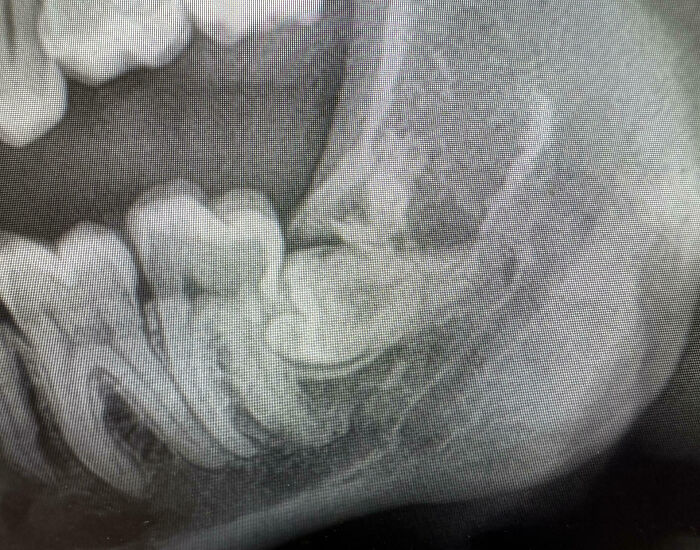

#3 My Wisdom Toot. You’d Think It Would Be Wise Enough To Not Do This Type Of Stuff

Image source: mdaws7